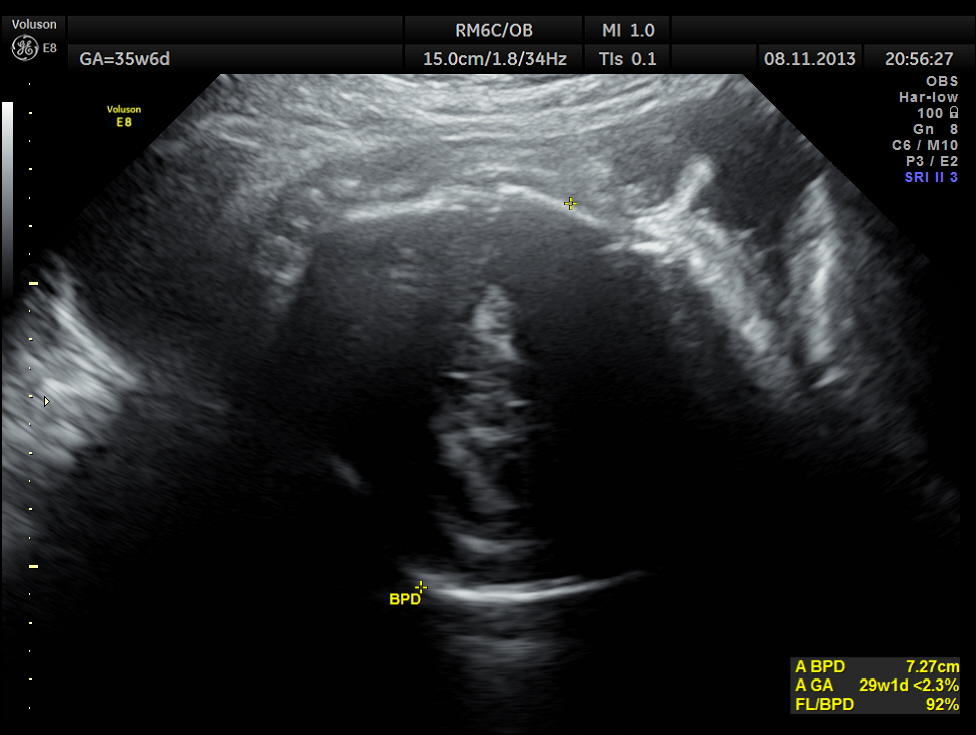

The scan was repeated at 36 weeks of gestation.

BPD, HC show < 2.3 % tile.